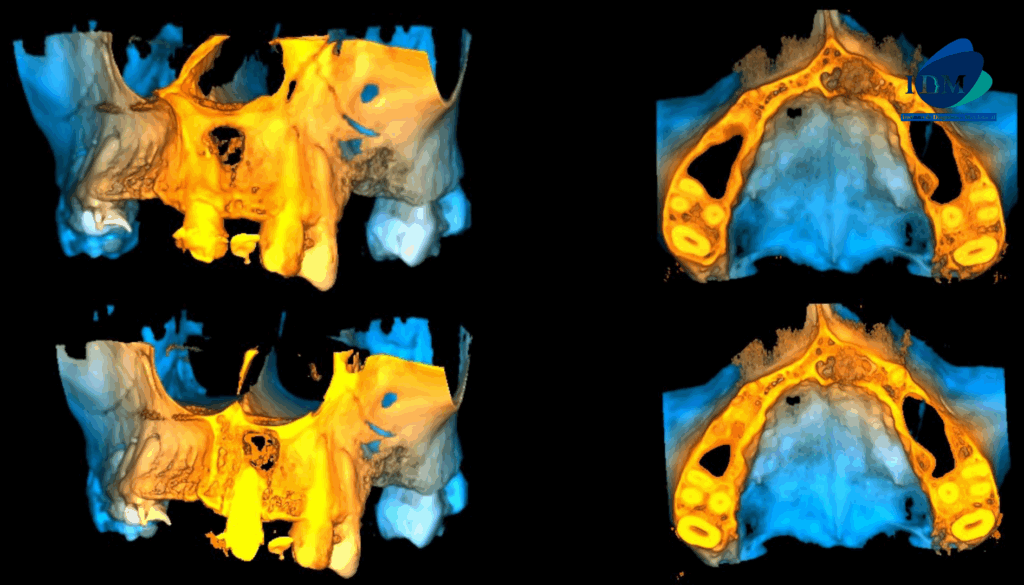

En las reconstrucciones 3D se representa de manera didáctica Lesión Fibroosea (Figura 4).

RECONSTRUCCIÓN 3D